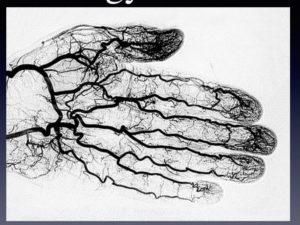

Первым признаком заболевания является видимый венозный рисунок. Он может появиться на внешней стороне кисти, на предплечье, на всей руке.

Фото симптомов на руках наглядно демонстрирует этот признак:

Развитие патологического процесса сопровождается кровяным застоем, в результате чего формируются узелки на венах рук. Расширение вен и образование уплотнений начинается с кистей и постепенно поднимается вверх. Сосудистые нарушения могут коснуться нижних фаланг пальцев.